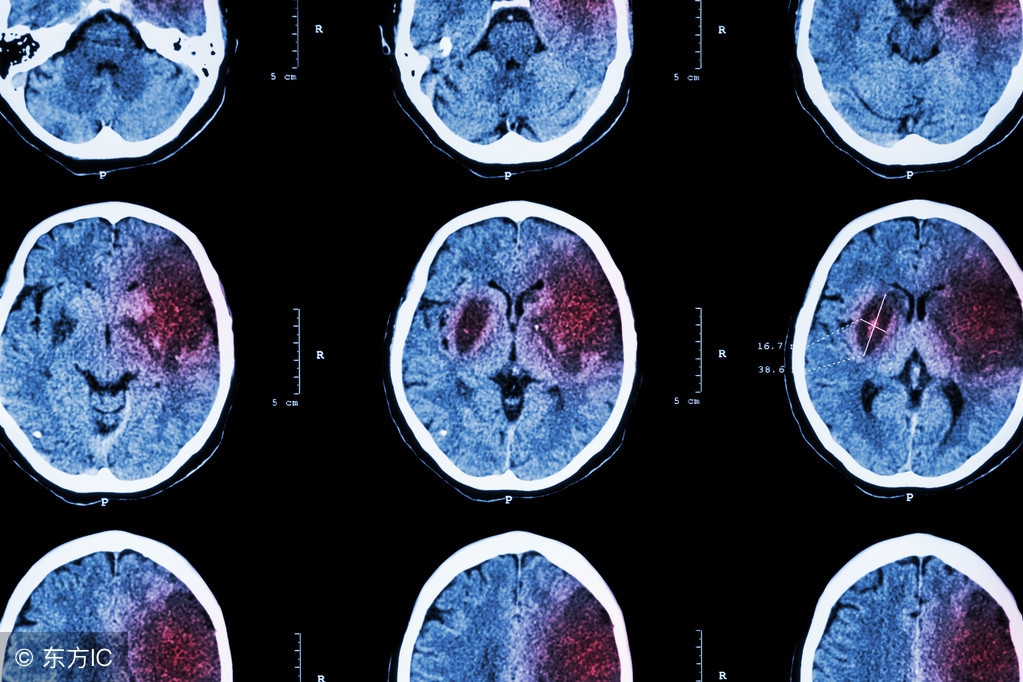

脑梗塞和脑溢血发病时的症状

脑堵塞发病时会产生偏瘫半身不遂、肢体麻木、偏盲、失语的症状。有时候也会产生语言障碍,而且还会造成记忆力下降的现象发生。很多的脑堵塞的患者还有口眼歪的症状。而脑溢血产生多是在情绪比较激动的情况下发生的。脑出血发病比急,可能在几个小时内就会造成患者的死亡。脑出血在发病前一般是没有什么先兆的。

脑出血病人发病后常有头痛,呕吐,血压高的现象,一些患者也会出现一些意识上在的障碍现象。还有比较简单的观察方法就是,脑出血的患者在发病的时候,眼部会有比较大的变化。有些患者会出现双瞳孔缩小和眼球同向偏视的现象。所以当身边的人突然的出现以上这些症状的时候要引起重视,应该马上让病人平躺下来打120或者是直接送医院,避免错过最佳的治疗时间。

如果患者同时发生了这脑出血有脑堵塞疾病的话,是要先治疗了脑部出血症状的。因为脑部出血是比较危险的,如果不能得到及时的治疗的话,流出的血液很容易积压在大脑里面,对生命产生威胁。造成脑溢血的病因有几种,病因不同治疗的方法也是不同的。如果是高血压引起的脑出血,首先是要先控制患者的血压。预防再次出血。如果是蛛网膜下腔出血,那就要排查是否有动脉瘤。等到控制血溢血现象后,后期可以通过中医的针灸进行排除脑部的淤血。